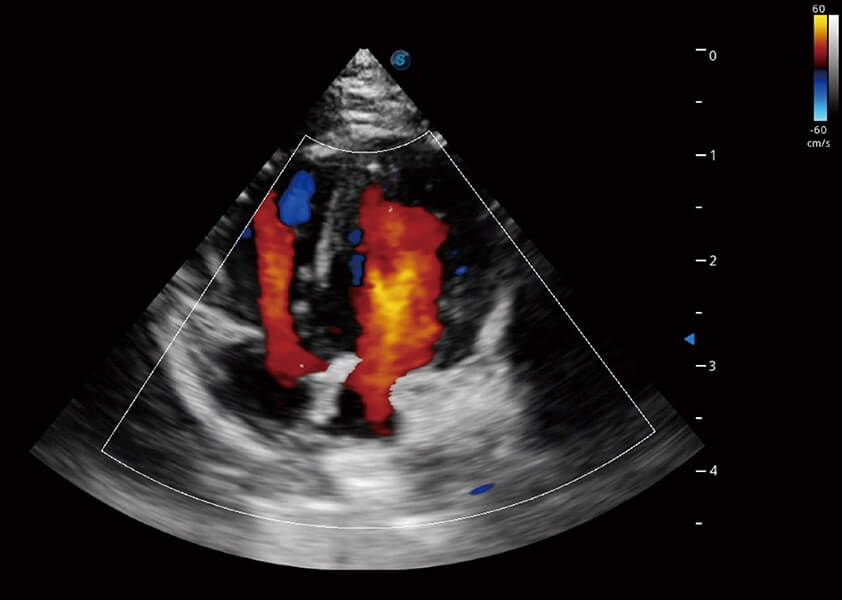

ProPet 60 作为一款高端台式动物超声设备,为动物医生的日常诊断提供了一系列贴合动物临床需求、解决临床实际问题的高级成像功能。凭借全系列高清探头,满足医生对腹部、心脏、生殖、浅表、肌骨等成像的所有需求,切实帮助您提升检查效率,提高诊断信心。

动物是人类最亲密的朋友和最值得信赖的伙伴。db真人体育官网也一直致力于探索动物专用的超声影像解决方案。 全新推出的ProPet系列,是db真人体育官网在动物超声影像智能化、专业化、精准化的一次跨越式革新。动物不能用言语来表述自己的不适,通过超声影像,ProPet系列搭建了动物医生与不同物种沟通的“桥梁”,为动物医生注入了“治愈之力”。